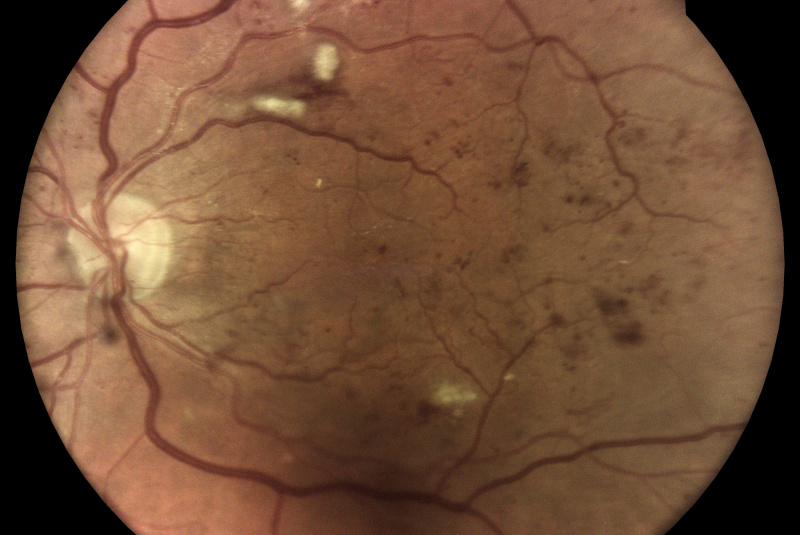

Z vysoko kvalitných fotografií očného pozadia zaobstaraných technológiou iCare DRSplus diagnostikuje diabetickú retinopatiu pomocou umelej inteligencie. Efektívny skríning vyhodnotený softwarom využívajúcim umelú inteligenciu iCare RETCAD®, je schválený pre klinické použitie a je klasifikovaný podľa certifikácie CE (0344) ako zdravotnícky prostiriedok triedy IIa, ktorý šetrí drahocenný čas ako lekára, tak aaj pacienta, umožňuje včasnú intervenciu a pomáha poskytovať včasnú starostlivosť. Analýza pomocou iCare RETCAD® nenahradzuje vyšetrenie zdravotného stavu očí.

AI (umelá inteligencia) okamžite rozpozná práznaky diabetickej retinopatie a klasifikuje výsledky podľa závažnosti na základe medzinárodných klasifikácií. Získate prehľad s hodnotením závažnosti záchytu, kde po analýze snímok zachytených kamerou iCare DRS Plus je automaticky generovaný report o pacientovi so stupnicou závažnosti pre diabetickú retinopatiu na základe medzinárodných štandardov (ICDR, AREDS).

Fundus kamera iCare DRSplus urobí celkovo 4 vysoko kvalitné True Color snímky (dve z pravého a dve z ľavého oka), ktoré sa automaticky ukladajú na cloud a posielajú sa na spracovanie AI - umelej inteligencii. Report je dostupný ihneď a ten je možné prekonzultovať s pacientom počas tej istej návštevy u lekára.